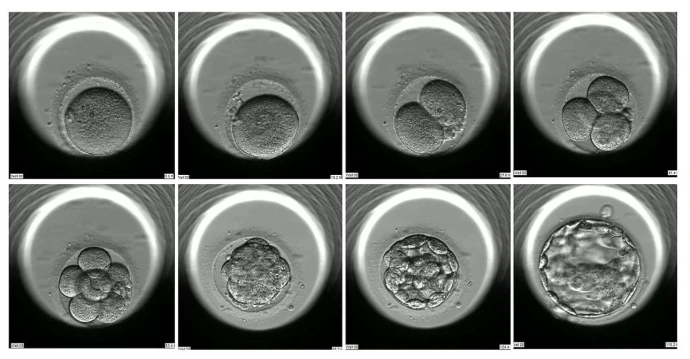

Artificial Intelligence AI Choosing your healthy BABY

AI embryoscopy is a new technology in IVF to help choose the best embryos for pregnancy. It uses smart computer programs to study how embryos grow and find the healthiest ones.

This makes the process faster, more accurate, and increases the chances of success. With AI embryoscopy, more families can achieve their dream of having a baby.